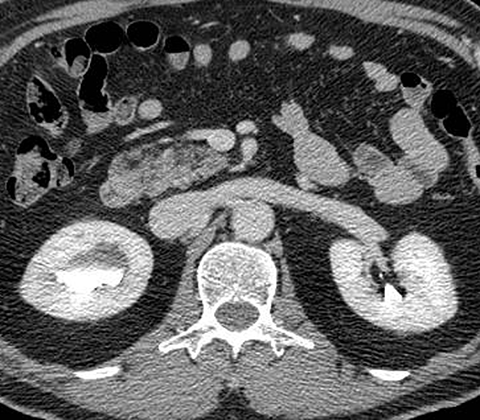

65-year-old male with painless hematuria [4 of 5]